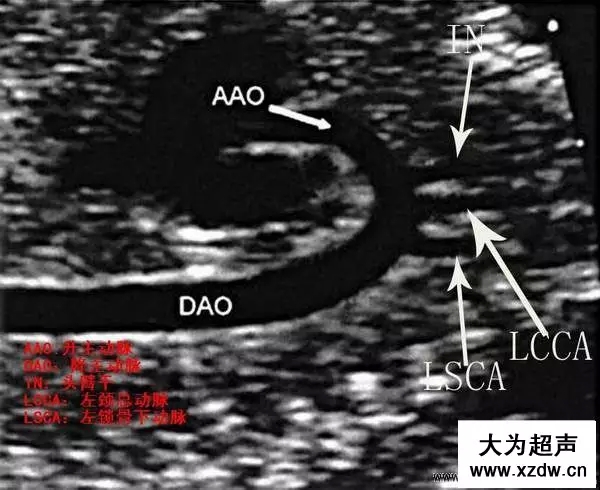

產科超聲正常圖片